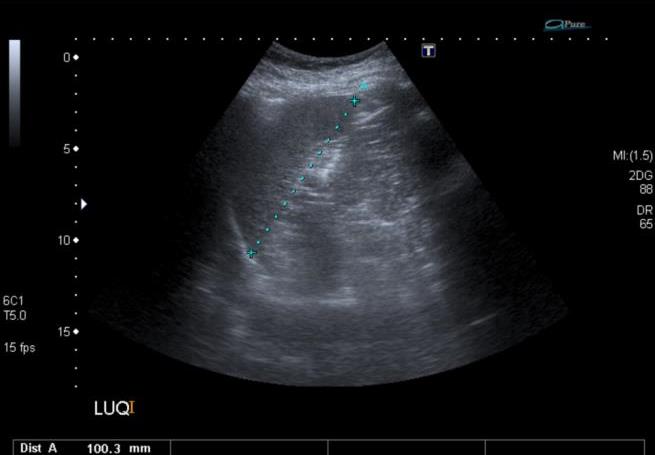

Representative sonographic images of the abdominal scan are shown below:

![]() |

Figure 1. Longitudinal image of the spleen |